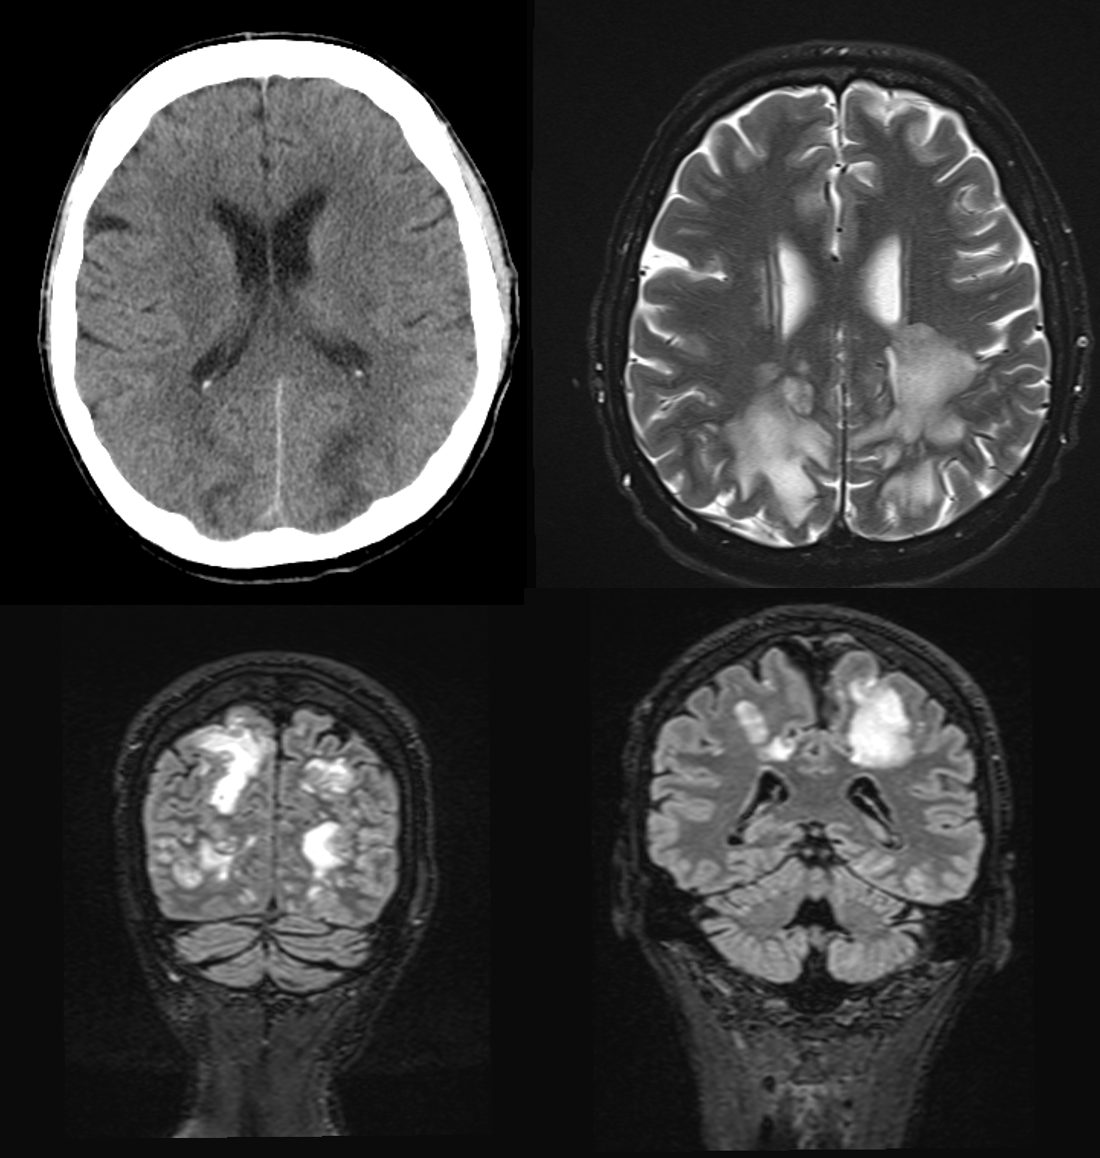

Eine Computertomographie des Kopfes erfolgte zum Ausschluss einer intrakraniellen Blutung. Aufgrund des pathologischen Befundes wurde im Anschluss eine Magnetresonanztomographie durchgeführt. Medical Case - Aymen - Hypertensive Crisis Nicotine.png

Die axiale T2 sowie die koronale T2-FLAIR Sequenzen zeigen ausgeprägte flächige T2w-hyperintense Areale im parietookzipitalen Marklager beidseits. Der Kortex ist nicht betroffen. Darüber hinaus kein Nachweis einer intrakraniellen Blutung. Bild vereinbar mit vasogenem Ödem bei Posteriorem reversiblem Enzephalopathie-Syndrom (PRES).